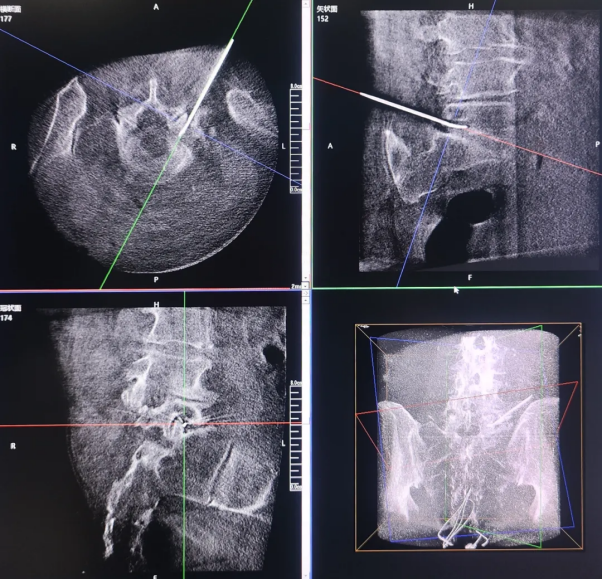

Radiofrequency Thermocoagulation of the Trigeminal Gasserian Ganglion

Radiofrequency Ablation of the Lumbar Dorsal Root Ganglion

Spinal surgeries in pain management focus on neuromodulation, requiring precise planning of the puncture path while carefully avoiding blood vessels, nerve roots, and visceral structures.Given the complex anatomy of nerves and blood vessels surrounding the spine, the inherent superimposition of structures in conventional 2D imaging may cause misinterpretation.

The 3D C-arm can generate intraoperative three-dimensional spinal images and CT-like cross-sectional views, providing physicians with a more comprehensive perspective for observation and clinical diagnosis.